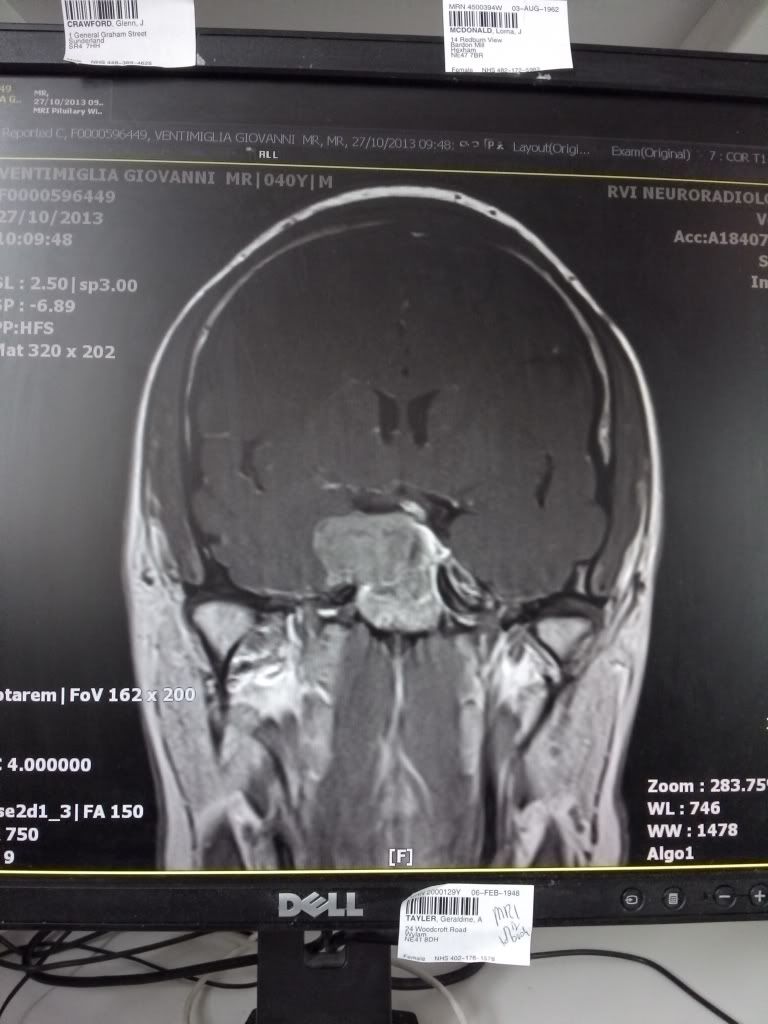

Been a bit laid up latley with illness and not been around much.Operation looming on the 20th to remove the growth under my brain.I want it pickled in a jar after for a keeps sake,yep I'm a sicko

Speaking of tripping stuff in one's head, we're all crossing everything that crosses for a complete success and rapid recovery. I'm much too intimately familiar with neuro-problems lately, based on what I can see from the scan yours resembles something my nephew went through a few years back. Smooth as silk, flying colors, nary a hitch. These docs know their bid'niss. I have every confidence that you'll be 100% fine, it's the sort of thing that's best dealt with head-on (no pun) and put behind you. Keep us posted as you're able, we'll be thinking of you.